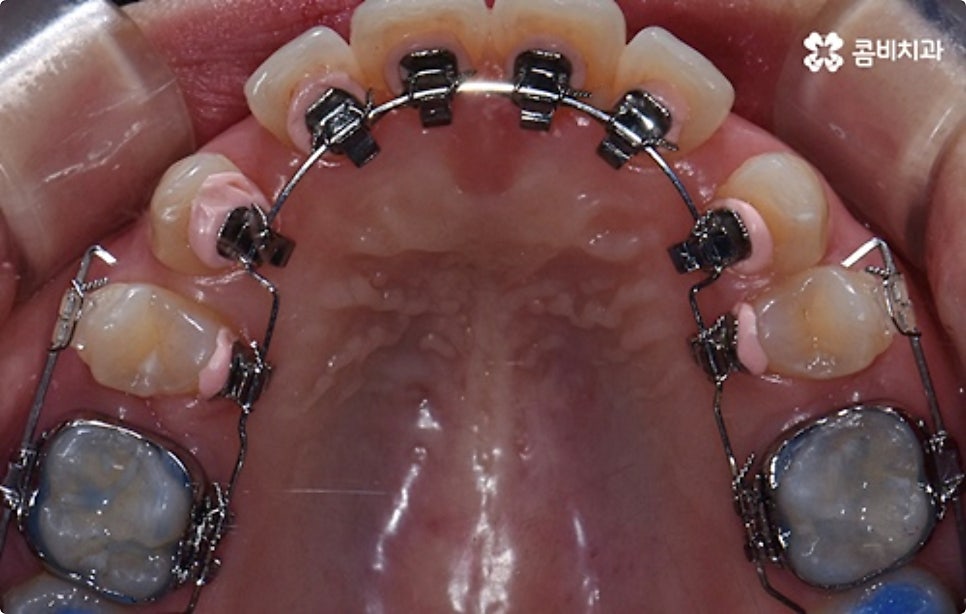

클리피씨 교정도 치아 색상의 세라믹 재질을 사용하기 때문에 심미성이 높은 편이지만 만약에 장치가 아예 겉으로 드러나지 않았으면 좋겠다고 생각하신다면 브라켓을 치아 안쪽에 부착하는 설측교정을 이용할 수 있는데요. 하지만 설측교정은 혀와 맞닿는 부분의 이물감, 통증, 발음상 문제 등을 일으킬 수 있기 때문에 잘 보이는 윗니는 설측으로, 잘 드러나지 않는 아랫니는 보통 교정과 같이 순측 (입술쪽) 으로 진행하는 콤비교정을 통해 이를 보완할 수 있어요. 사진에서 살펴보실 수 있는 케이스 역시 이렇게 콤비로 진행한 직장인치아교정 과정으로 시간이 지날수록 점차 치열이 가지런해지고 교합이 올바르게 개선되는 것을 확인해 보실 수 있습니다.